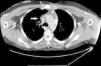

En la exploración física destacaba edema facial, dilatación de las venas del cuello e incremento del número de venas colaterales en la parte anterior del tórax, hombro y brazo derecho. En la radiografía de tórax se observó ensanchamiento del mediastino y derrame pleural subpulmonar bilateral. La tomografía computarizada (TC) de tórax mostró un mediastino ensanchado con trabeculación de la grasa y que ocasionaba un efecto masa que afectaba a la vena cava superior (fig. 1). La reconstrucción angiográfica en 3D mostró la extensa red de circulación colateral por obstrucción de la vena cava superior que se extendía hacia la pared torácica, los miembros superiores y el abdomen (fig. 2). No se evidenciaron trombos en la vena cava. Ante estos hallazgos, se diagnosticó como SVCS. Se realizó una flebografía para valorar la afectación vascular y colocar un stent endovascular con el objetivo de repermeabilizar la circulación venosa. Sin embargo, este tratamiento fue infructuoso debido a la existencia de una obstrucción total de las venas subclavias que dificultaba el acceso a la vena cava. Dada la obstrucción de la vena cava superior por un proceso infiltrativo mediastínico, se realizó mediastinotomía para filiar la causa responsable de dicho proceso. La biopsia mostró un tejido adiposo con escasa celularidad sin que se identificaran granulomas, calcificaciones ni células malignas. La prueba de la tuberculina no mostró induración, y el cultivo para micobacterias y hongos del broncoaspirado y del material de la biopsia fue negativo El paciente fue diagnosticado de SVCS por fibrosis mediastínica de origen idiopático.